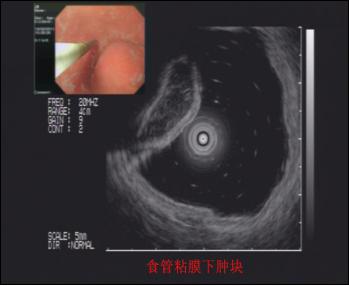

超聲內(nèi)鏡技術(shù)